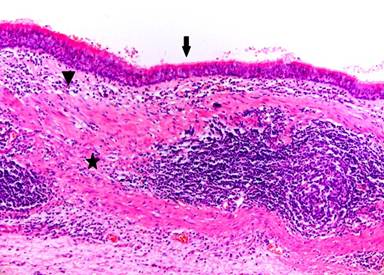

A fifty-two-year-old female was evaluated for abdominal pain. She had a vague history of upper and left sided abdominal pain for 6 months. An ultrasound showed a cystic lesion in the left upper abdomen. A CT scan subsequently confirmed the presence of a large 10 cm cystic lesion in very close proximity to the spleen and the pancreas. The lesion reached close to the neck of the pancreas. The lesion involved the mid-body / tail of the pancreas, was abutting against the spleen (Figures 1 and 2). There was close proximity to the splenic vein, although the vein was patent. The splenic artery was close but seemed uninvolved (Figure 3). The cyst wall was uniform. There were no internal septations or any other features to suggest an intracystic solid component or bleeding. There were no calcifications with the cyst. The rest of the pancreas appeared normal with no evidence of pancreatitis. There were no gall stones or any other biliary abnormality. Clinicoradiologically it was felt to be a large cyst possibly a splenic cyst. However given the fact that she was symptomatic, we decided to proceed with a laparoscopic resection. All her blood tests including tumour marker profile (CA 19-9 and CEA) were normal. She underwent a laparoscopic distal pancreatectomy with splenectomy. At laparoscopy we discovered a large cystic lesion occupying the lesser sac and abutting against the spleen. The pancreas could not be separated off the cyst. We completely mobilised the stomach off the cyst and the pancreas, to completely expose the pancreas with the cyst in the lesser sac. We completed a distal pancreatectomy with splenectomy laparoscopically, with complete enbloc excision of the cyst (Figure 4). Post-operative recovery was uneventful and the patient was discharged 4 days following surgery. Gross pathology showed a 90x50x60 mm cystic lesion, attached to and arising from the inferior and posterior aspect of the pancreas. On pathology the rest of the pancreas appeared normal and the splenic capsule was not breached. The histology of the cyst showed the presence of pseudo stratified ciliated columnar epithelium , overlying some connective tissue (Figure 5; H&E, magnification x10) .Similar features were confirmed on the high powered images of the cyst wall as well (H&E, magnification x20). Based on these characteristic and rather unusual histological features, the diagnosis of a ciliated foregut cyst of the pancreas was established.

Figure 5. Low powered image of the cyst showing a thin layer of epithelium (Arrow) covering the loose sub epithelial connective tissue (arrow head) and Smooth muscle layer (star). (H&E, magnification x8/10). |

The diagnosis of a ciliated foregut cyst of the pancreas therefore remains a pathological diagnosis, obtained only upon a definitive histological evaluation of the resected specimen. Woon et al., in a review of cytospin smears in their case, identified detached ciliary tufts (DCT), within cohesive clusters of cuboidal to columnar cells [7]. There was no mucin in the cytoplasm of these cells [7]. They concluded that the presence of DCTs in the cyst fluid is conclusive for the diagnosis of a ciliated foregut cyst [7]. This is in keeping with the finding of DCTs within the aspirates of foregut cysts within the mediastinum, where they are more common and wherein most of the experience in cytological evaluation of cyst fluid comes from [11]. A total of 14 cases of ciliated foregut cysts of the pancreas have been reported in English medical literature thus far [6, 7, 11]. In our patient, the presence of pseudo-stratified columnar epithelium along the cyst wall along overlying a layer of loose connective tissue was suggestive of this diagnosis. The cyst was attached to and appeared to arise from the posterior and inferior wall of the pancreas, which was in keeping with its pancreatic origin. Woon et al. summarised these cases in their publication [7]. However they mentioned that upon review of the proposed classification mechanisms, only 2 cases could be truly classified as ciliated foregut cysts, which makes this entity even rarer [7]. These are considered benign lesions [7]. The most common radiological differential diagnosis would be a mucinous cyst of the pancreas. However, we feel that any patient with a symptomatic pancreatic cyst merits treatment and hence an appropriate resection should be offered wherever necessary. Where the possibility of a pancreatic pseudocyst as a differential exists, in keeping with the guidelines, an EUS with fluid aspiration and cytologic analysis should be carried out. We however feel, given the rarity of the condition, although theoretically it may be possible to establish a diagnosis of ciliated foregut cyst of the pancreas based on the presence of DCTs, in practice this may not be possible. Hence the diagnosis is purely at final histopathology and standard algorithms of pancreatic cyst management should be followed when evaluating such patients.